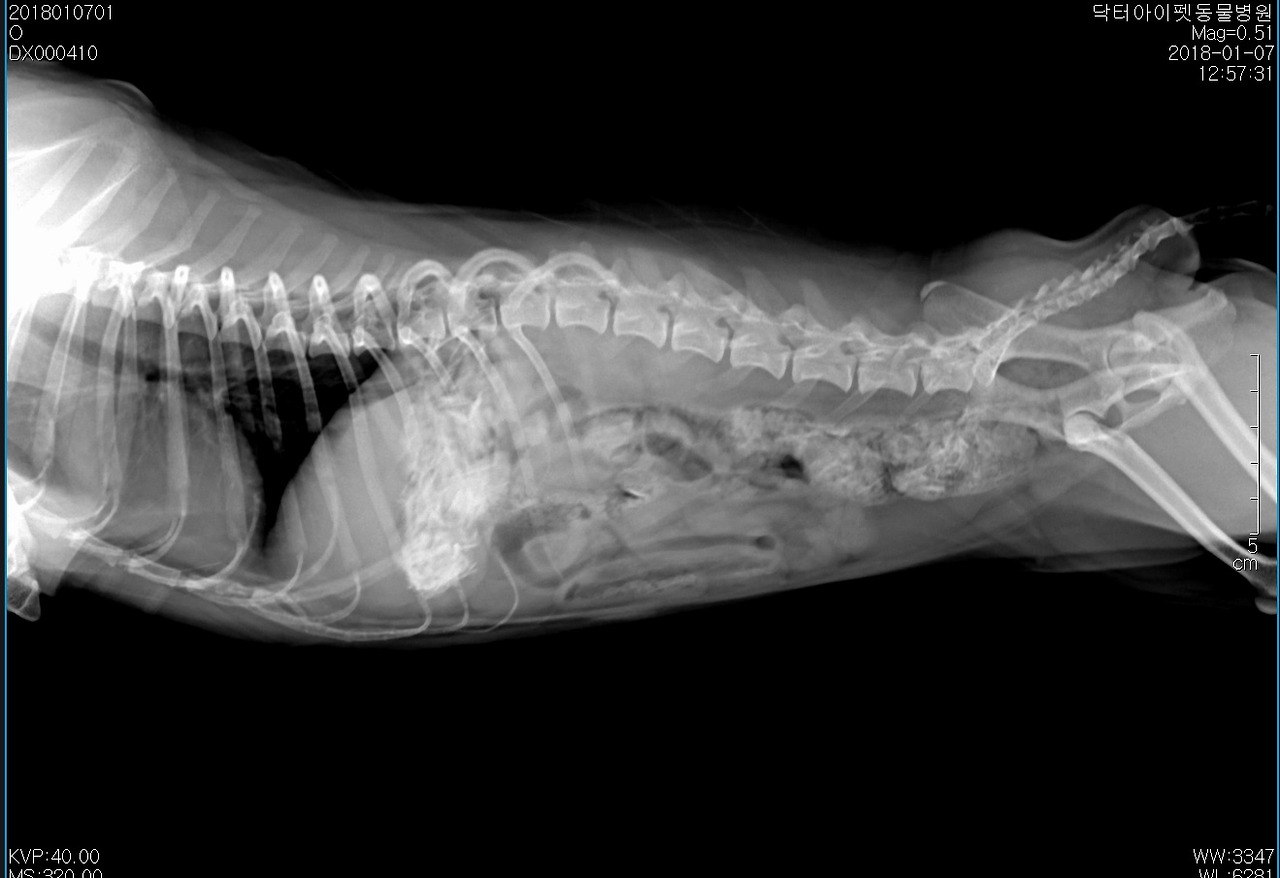

엑스레이를 찍어봤다. 위 한 가득 치킨 뼈가 차있었다. 일반적인 케이스라면 수술을 우선적으로 고려했을 거다. 다행스럽게도 띠띠는 침을 많이 흘리거나 출혈성 구토, 혈변 등의 증상이 없었다. 절대 금식을 당부하고 3일 통원치료를 계획했다. 72시간 정도 경과하면 대부분 섭취한 음식물은 소화되기 따름이다. 기대한 대로 대부분 소화되어 대변으로 배출되었다.

통원 1일, 2일, 3일차 방사선 사진. 다행이었다. 뼈는 모두 소화되고 배출되었다.